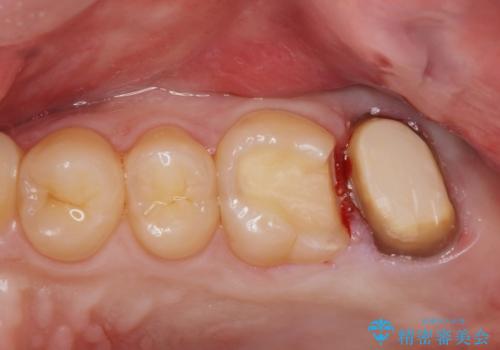

適合の良い被せ物が入りました。

ゴールドの被せ物は適合がよく虫歯の再発のリスクが低くなります。

また根の治療を行う時はラバーダムを行い治療しています。